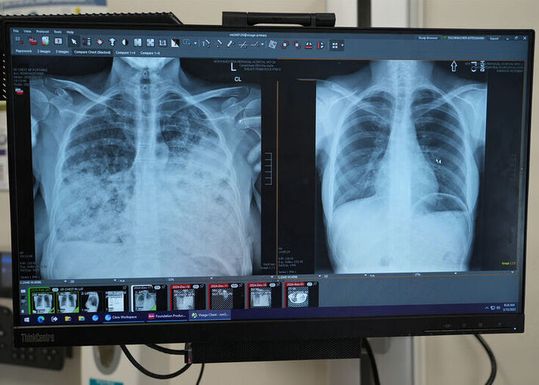

Lung cancer patient scans before and after transplant.

(Source: Northwestern University)